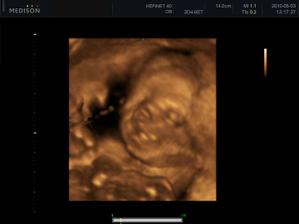

Náš zázrak